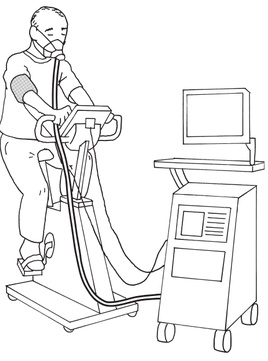

68 歳の男性。急性心筋梗塞のため 14 日間入院し、退院後 2 か月が経過した。心臓リハビリテーションのために実施した検査場面を図に示す。測定項目に含まれないのはどれか。